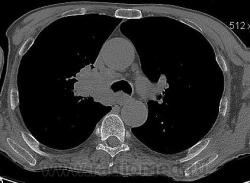

Мужчина 69 лет, с последствием ОНМК находился в доме-интернате для инвалидов. В анамнезе пневмония справа и исходом в пневмосклероз. ФЛГ не проходил 1.5 года. Анализы: СОЭ 20 мм/ч, остальное - без особенностей. Поступил в неврологическое отделение с диагнозом: повторное ОНМК. Невролог заподозрил метастазы головного мозга, направил на рентгенографию легких. После выявленых изменений в правом легком, пациент направлен на КТ головного мозга и грудной полости. От контрастирования и бронхоскопии категорически отказался.

По поводу подозрения на туберкулез пациента в прошлом нодократно проверяли, исключили. ФЛГ архива у меня нет. Все только со слов пациента. Кальцинаты в корне массивные. Трудно сказать, откуда опухоль (если это не конгломерат лимфоузлов!) плотностью 35 ед.Н - то ли из вехнедолевого бронха, который имеет культю 0.4 см и заканчивается выпуклым контуром, но при этом сохраняется воздушность почти всей доли; то ли периферический с центром в прикорневой зоне и вторичным прорастанием ВДБ. К сожалению забыла про снимок легких, на днях выставлю. Я первоначально считала периферический (верхушка, на фоне пневмосклероза) с мтс средостения. По плотности на верхушке узелок 5 ед.Н, только поэтому засомневалась, где же первичный. Лимфоузлы средостения множественные, до 2 см. Кроме того, на верхней стенке правого главного бронха есть мелкое образование такой же 35 е.Н плотности, то ли аденома, то ли прорастает... Без бронхоскопии - только гадать

это периферический рак S2 в/доли правого легкого с мтс во внутригрудные л/узлы.

А тут нечего гадать - данную демонстрацию можно поместить в учебник: узловое образование, с бугристыми, лучистыми контурами, связаное с плеврой, "дорожкой" к корню, перифокальной инфильтрацией. Корень расширен полицикличен за счет конгломерата увеличеных бронхопульмональных, трахеобронхиальных и бифуркационных л/узлов, значительно сдавливающих в/долевой бронх, с нарушением вентиляции в/доли.

Центральный рак ВДБ справа с мтс в л/узлы паратрахеальные нижние, верхние справа, БФ. МТС в головной мозг. А про печень мало сканов

Мне кажется в 6 сегменте печени мтс + еще мтс поражение левого надпочечника вероятнее всего. Мтс в нижние паратрахеальные (с обеих сторон)+бифуркационные л/у. Поражения верхних паратрахеальных не вижу (на коронарах), аксиалы - не показыны сканы выше верхнего края дуги аорты, так что я бы не говорил про поражение верхних медиастинальных лимфоузлов (хотя тут это уже не принципиально) + мтс в головной мозг. А так - центральный рак правого легкого.